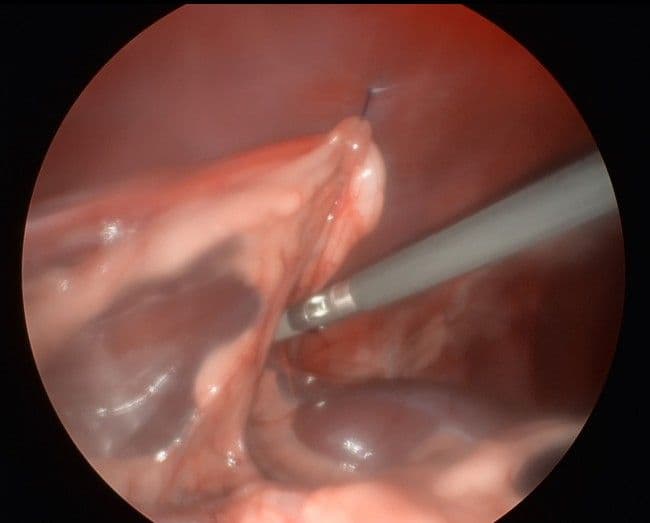

실제 수술 및 시술 사례

최소 침습으로 진행되는 복강경 수술의 실제 모습입니다.

정밀 수술 시야